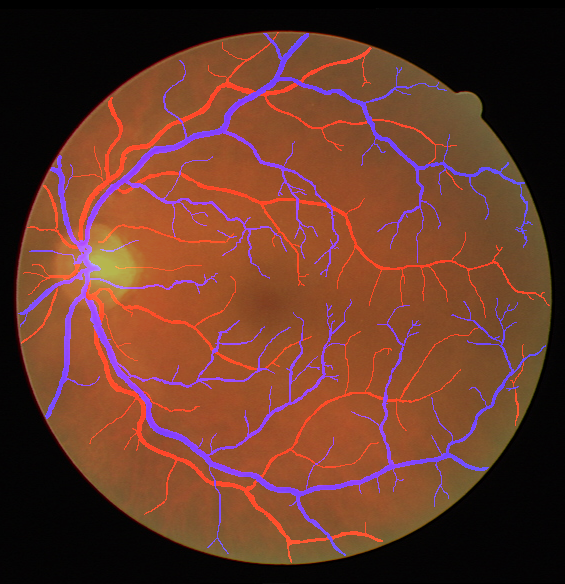

Table V presents quantitative performance benchmarks of SegRAVIR and other competing approaches for retinal artery and vein classification on the RITE dataset [11]. SegRAVIR outperforms previous state-of-the-art approaches in terms of accuracy, sensitivity, and specificity. Fig. 5 provides a qualitative comparison between segmentation outputs of SegRAVIR and the method of Hemelings et al. [40] on the RITE test set.

VI-B Vessel Width Estimation